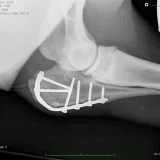

- Advanced osteosynthesis